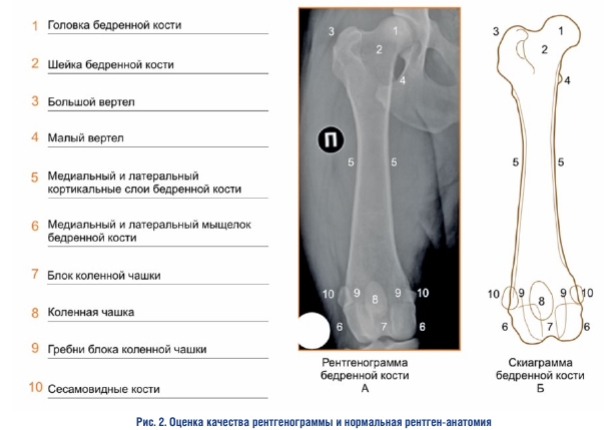

Оценка ортопедической проекции — дистальный эпифиз. При интерпретации правильной ориентации дистального эпифиза бедренной кости во фронтальной плоскости необходимо учитывать усредненную совокупность признаков, каждый из которых по отдельности не является абсолютным критерием адекватности проекции (рис. 3)

Положение сесамовидных костей. Сесамовид- ные кости должны быть разделены кортикальными слоями пополам. Сесамовидные кости являются структурой, которая относится к бедренной кости, но не принадлежит ей, поэтому, например, при изменении формы сесамовидных костей, при наличии остеоартрита сезамо-бедренных суставов, данный критерий может не отражать истинного положения дистального эпифиза бедренной кости.

Положение межмыщелковой ямки и контуров мыщелков. Межмыщелковая ямка должна иметь форму равномерно вогнутой окружности. Контуры латерального и медиального мыщелков должны хорошо визуализироваться, быть прямыми и располагаться посередине относительно ширины дистального эпифиза.

Положение коленной чашки. Коленная чашка должна находиться в своем нейтральном положении относительно блока коленной чашки на линии, соединяющей сесамовидные кости, и делить коленную чашку на примерно равные верхнюю и нижнюю части. Такая ориентация коленной чашки свидетельствует о параллельном положения бедренной кости относительно рентгеновской кассеты (фронтальной плоскости).

Оценка ортопедической проекции — проксимальный эпифиз. При интерпретации правильной ориентации проксимального эпифиза бедренной кости во фронтальной плоскости необходимо учитывать усредненную совокупность признаков, каждый из которых по отдельности не является абсолютным критерием адекватности проекции 1.

Положение малого вертела. Малый вертел должен хорошо визуализироваться, иметь четкие контуры и точные границы, его медиальный край должен уверенно, но не избыточно выступать за границы медиального кортикального слоя бедренной кости.

Визуализация большого вертела. Большой вертел должен хорошо визуализироваться, иметь четкие контуры и точные границы.

Визуализация шейки и головки. Головка и шейка должны хорошо визуализироваться, иметь четкие контуры и точные границы.